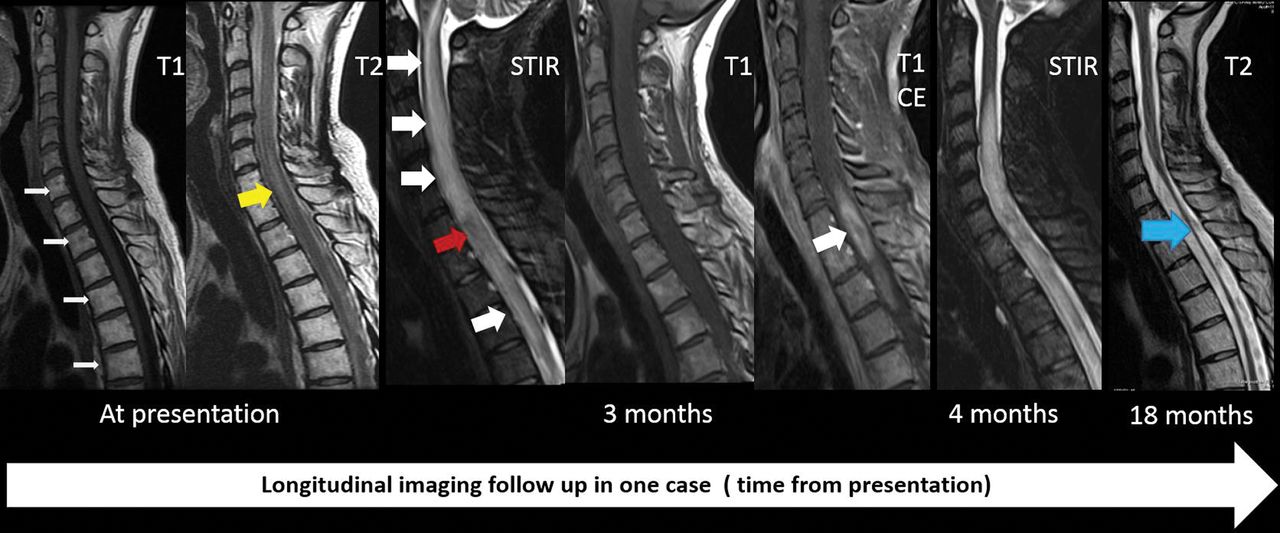

Our study is unique because follow-up imaging and clinical history were available in most of our patients, and on follow-up, cord atrophy was seen in only 25% of our cases, which suggests that the timing of MR imaging after radiation may dictate the imaging findings. One of the interesting observations in this study is resolution or a decrease in T2 signal changes (Fig 4), affecting 12.5% and 50%, respectively, on follow-up, especially because RM is thought to be irreversible and permanent. Although formal statistical analysis was not possible due to the rarity of occurrence and small sample size, our series suggests that clinical improvement may correlate well with imaging findings on longitudinal follow-up. Hemorrhagic changes, cord expansion, and contrast enhancement were variable and were noted in patients who were scanned early during the disease process, and tended to resolve on follow-up. This finding has not been well-reported, and our correlation with clinical history suggests that the extent of hemorrhagic changes may dictate the severity of neurologic symptoms at presentation and disability at follow-up.

Sequential changes on imaging in a patient with severe radiation myelitis. Fatty bone marrow changes present with hyperintense T1 signal involving C7 and the upper thoracic vertebrae on the first image (white arrows). Less extensive longitudinally extensive myelitis at the C7, T1, and T2 levels is noted on the T2-weighted image with hyperintense signal at presentation (yellow arrow). At 3 months, cord expansion and extensive T2/STIR hyperintense signal changes involving the cervical and upper thoracic cord are noted (white arrowhead) with contrast enhancement at the C7, T1, and T2 levels (single large white arrowhead). The patient was paraplegic with urinary and bowel incontinence. She was treated with a high dose of steroids. Follow-up images at 18 months show cord atrophy (blue arrow). She eventually was able to ambulate with a walker after extensive physical therapy. CE indicates contrast enhancement.